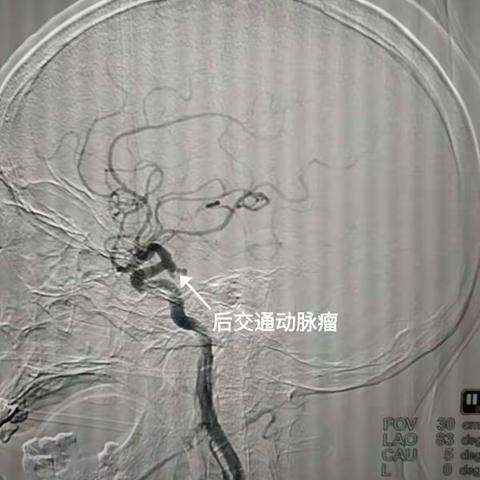

巧手摘除“颅内不定时炸弹”

2021-11-13

1380阅读